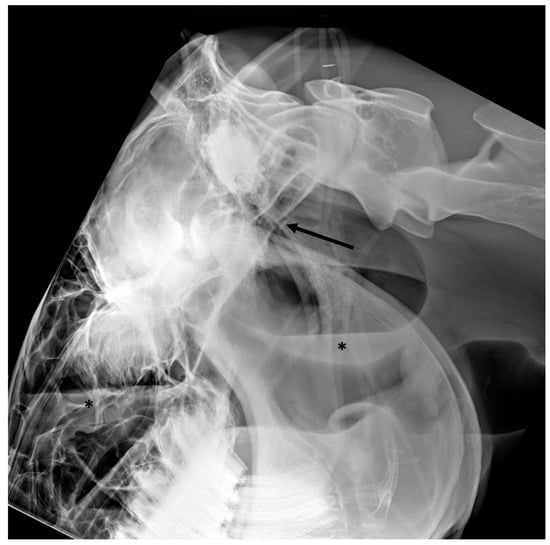

3.4. Temporohyoid Osteoarthropathy